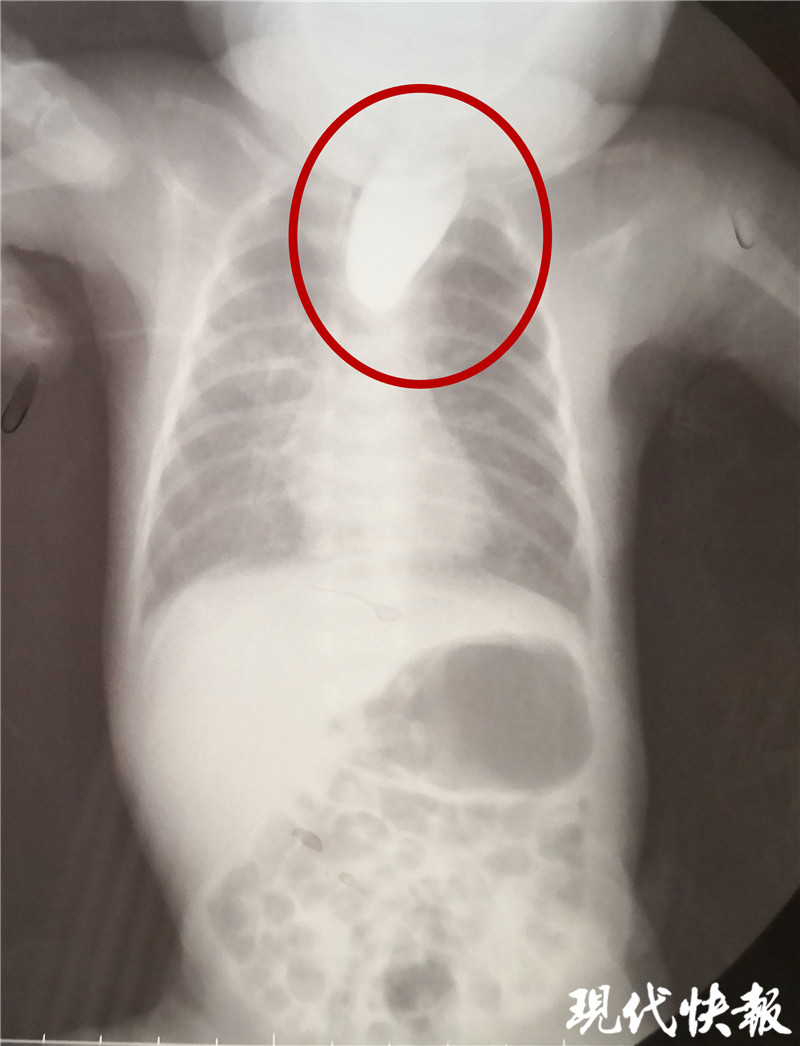

△食道閉鎖

現(xiàn)代快報(bào)記者了解到,9月8日,東東從當(dāng)?shù)蒯t(yī)院轉(zhuǎn)入淮安市婦幼保健院治療,檢查顯示東東的食道是個(gè)“死胡同”,明確診斷為食道閉鎖。“從片子上看,這個(gè)白色的造影劑到了食管上端就無法向下流了,說明孩子的食管上端是不通的、閉塞的。同時(shí),孩子腸腔里面有氣體,這個(gè)氣體是通過氣道到食管的遠(yuǎn)端,到達(dá)胃和腸道內(nèi)。”淮安市婦幼保健院小兒外科副主任醫(yī)師夏順林說,這個(gè)寶寶如果不及時(shí)手術(shù),就會(huì)面臨兩個(gè)問題,一個(gè)就是唾液咽不下去,會(huì)嗆入肺部形成吸入性肺炎,同時(shí)胃和食管遠(yuǎn)端與氣管相通,胃內(nèi)的胃酸容易反流到氣道里面,進(jìn)入肺部形成化學(xué)性肺炎。